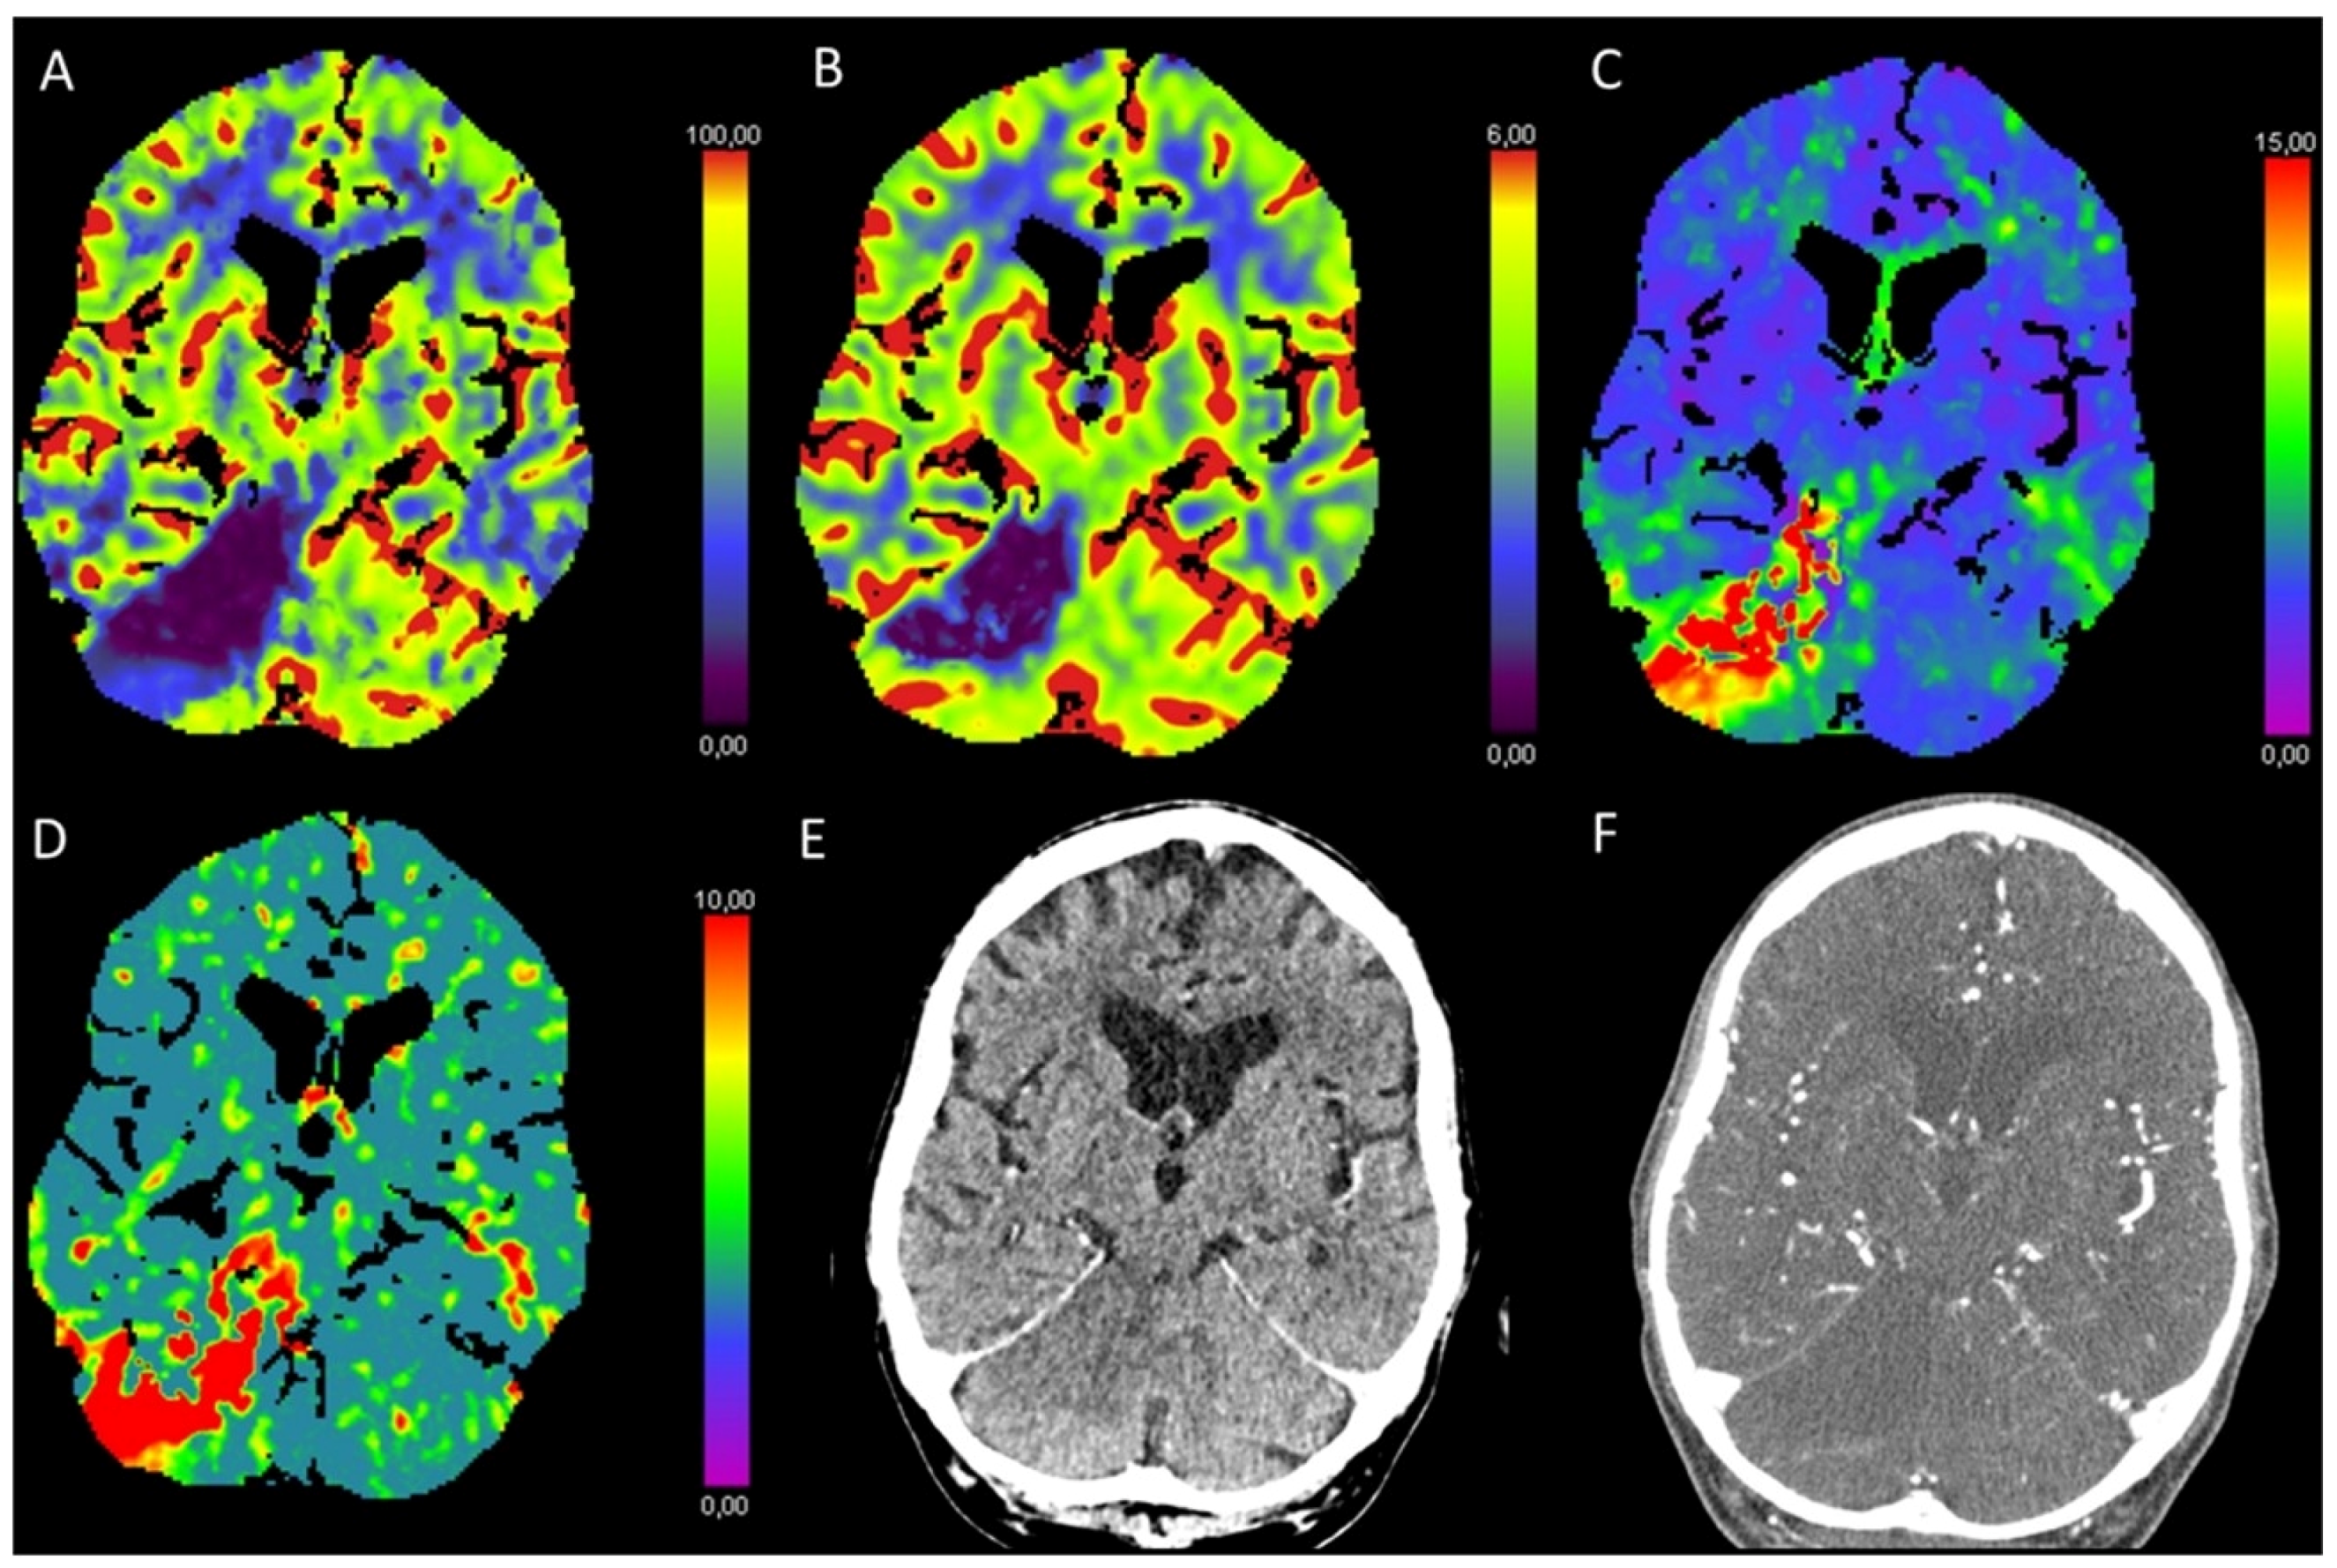

3.1. Acute Supratentorial Stroke